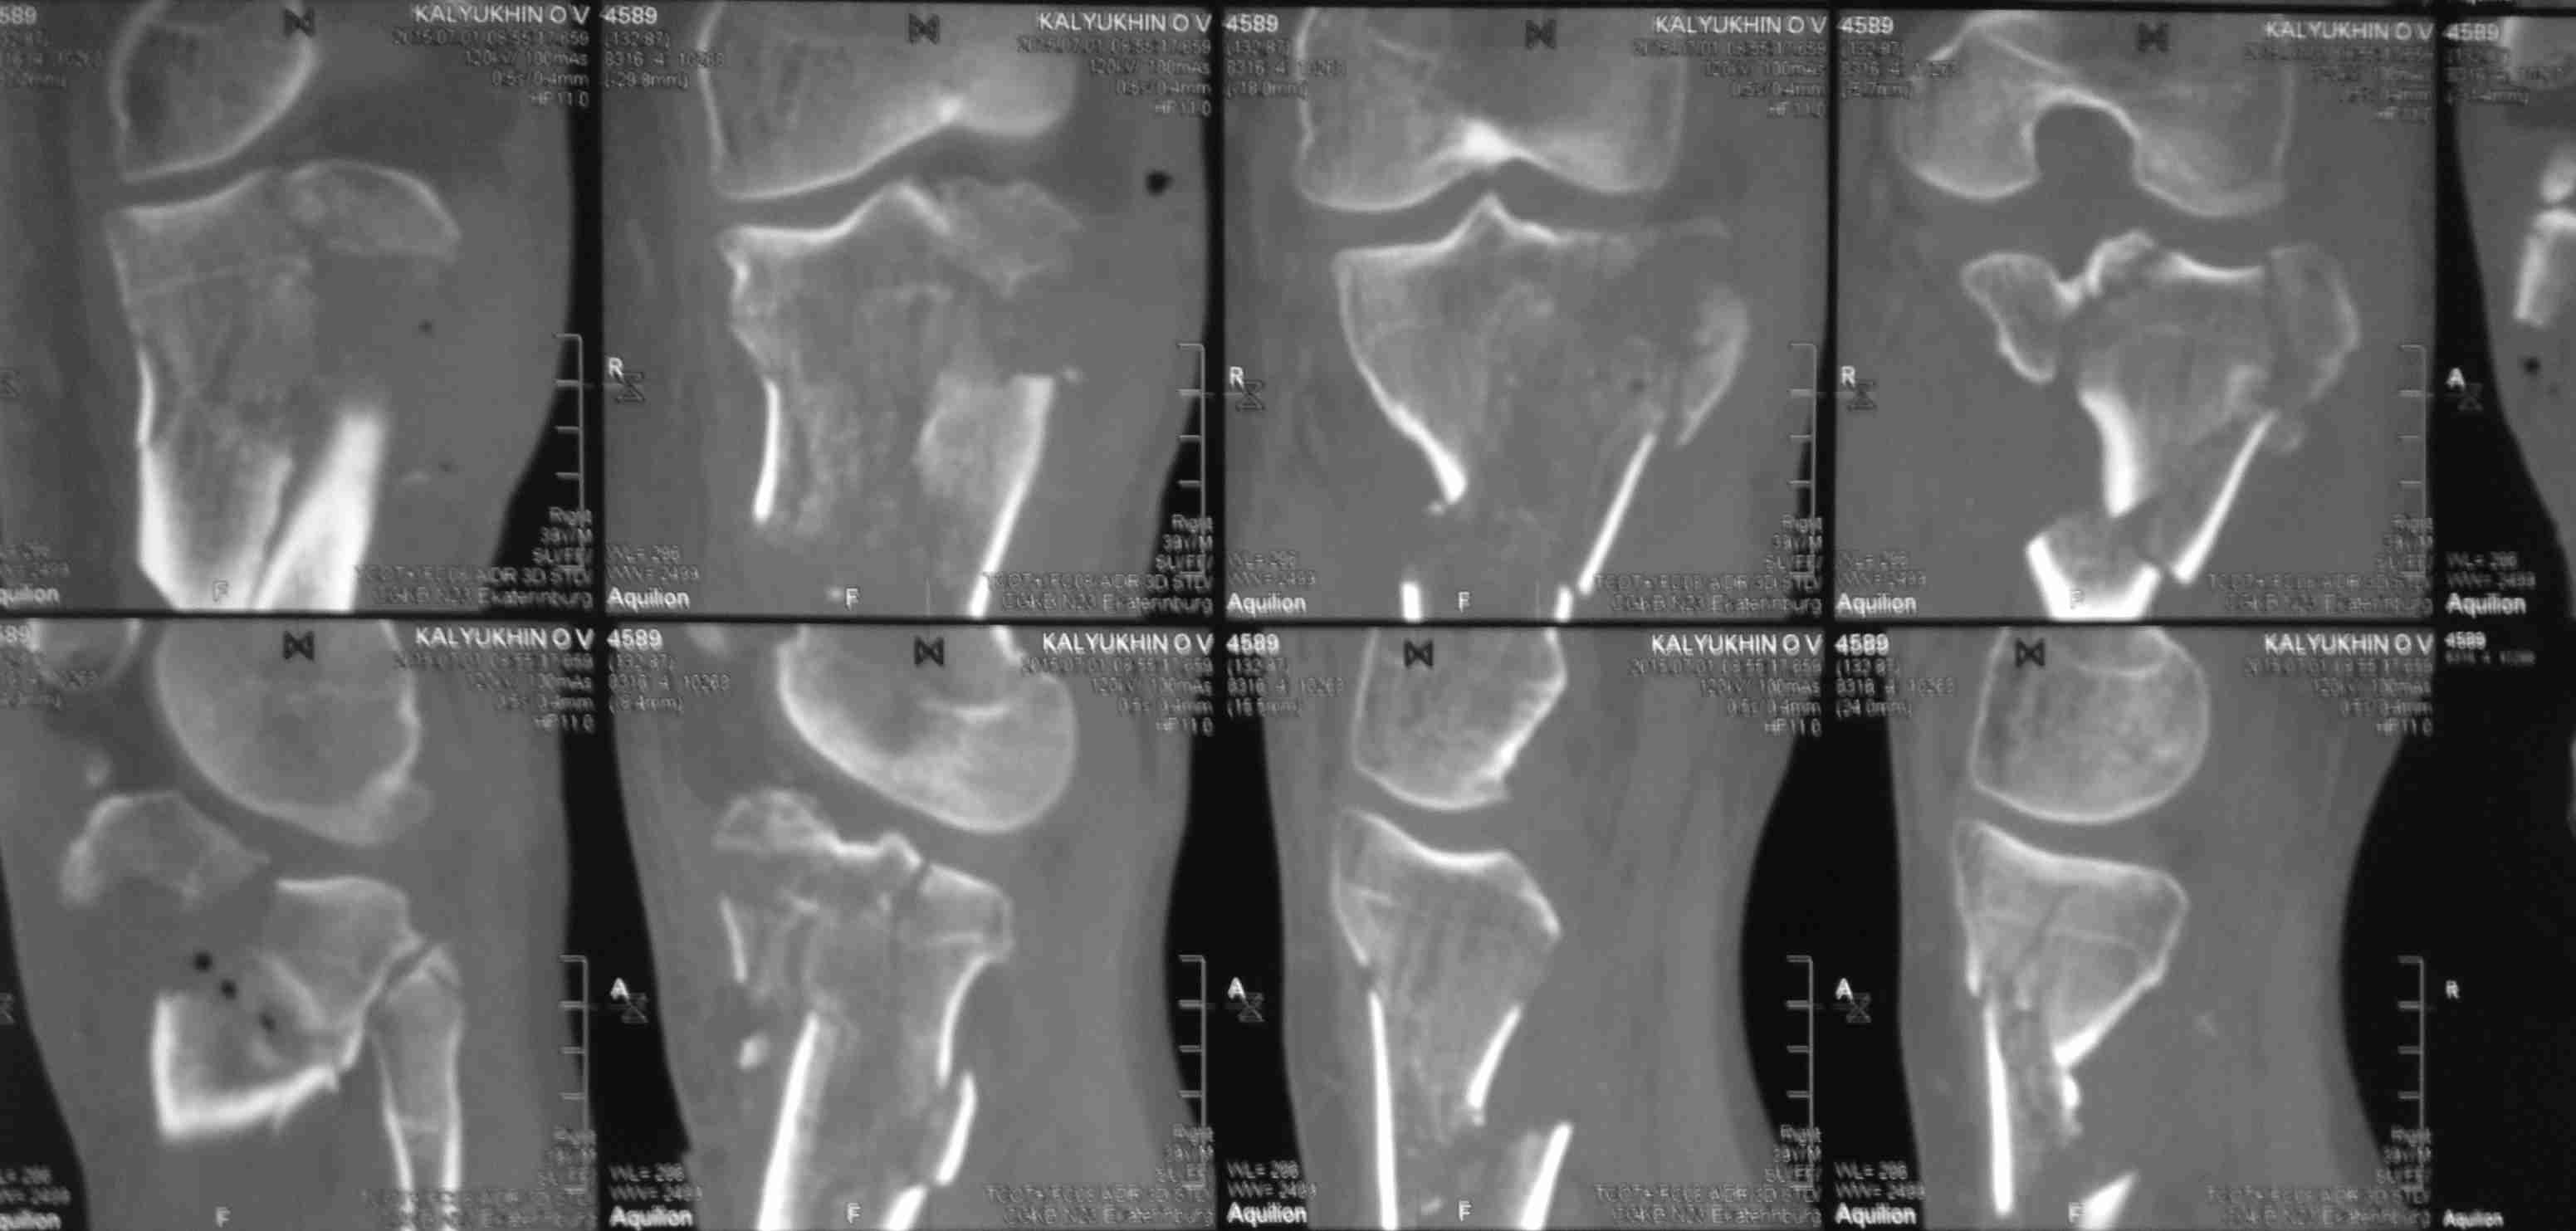

Серия КТ сканов в аппарате

Голень-41-С3.1 - полный внутрисуставной и метафизарный оскольчатый перелом с доминантным повреждением наружного мыщелка, с импрессией центральной части плато. Первичная тактика полный респект по АО и ОТА. на фоне лигаметотаксиса выполнено КТ, которое четко детализирует повреждение и определяет дальнейшую тактику.

Основная проблема не бугристость, а внутрисуставное повреждение латерального мыщелка с импрессией центральной части. С большей вероятностью, есть паракапсуллярное продольное повреждение наружного мениска.